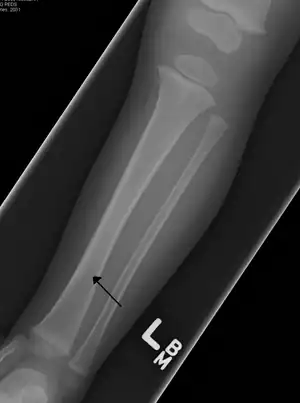

| Toddler's fracture | Toddlers | undisplaced spiral fracture of distal tibia in children under 8 years old | low-energy trauma, often rotational | The toddler's fracture revisited Archived 2016-03-03 at the Wayback Machine at Wheeless' Textbook of Orthopaedics online |

|